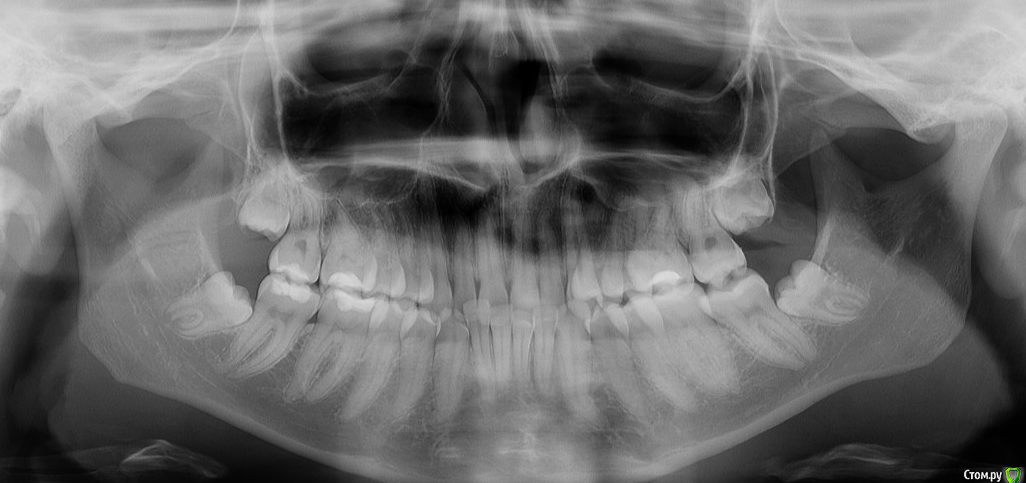

Ann15 Опубликовано 29 апреля, 2020 Поделиться Опубликовано 29 апреля, 2020 (изменено) Добрый день! Мне 23 года, хочу поставить себе брекеты. В связи с карантином удалось посетить только двух специалистов, мнения которых по поводу меня разошлись.1- ортодонт, к которой пошла почти наобум, по принципу "близко и вроде клиника неплохая". Сразу сказала о необходимости удалять восьмерки (все непрорезавшиеся, но все есть)2 - ортодонт с очень большим опытом и хорошими отзывами, она сразу проголосовала за мое лечение элайнерами, уверяя, что у меня ничего страшного, и случай нетяжелый. По итогу 3д диагностики насчитали 30 и 32 капы, что вышло в копеечку. Я начала сомневаться, что случай действительно легкий. Также на выбор мне предложили два плана моделирования (НЧ по итогу выдвигается вперед или не выдвигается) и сказали выбрать. 1) Может ли такое быть в ортодонтии? Разве не доктор должен определить, какой прикус правильнее с учетом истираемости зубов и т.п.? Если бы не опыт и рекомендации знакомых, точно бы засомневалась в квалификации. Не хочется из-за мнительности отказываться от лечения у хорошего спеца, неважно, на брекетах или элайнерах. По восьмеркам: сказала, что удалять не надо, если не хочу, и если удалить все-таки, то лечение будет более сложное и долгое2) Что в итоге надо делать с восьмерками? Я со своей непрофессиональной колокольни выступаю за "вырвать и забыть", но знаю, что некоторые врачи против удаления восьмерок. Действительно ли отсутсвие/наличие восьмерок не повлияет на ретенцию и может ли их отсутствие осложнить лечение?Снимок прикладываю Изменено 29 апреля, 2020 пользователем Ann15 Ссылка на комментарий

red_butler Опубликовано 29 апреля, 2020 Поделиться Опубликовано 29 апреля, 2020 Ваши третьи моляры удалять по любому. Данный раздел требует больший объём данных http://forum.stom.ru/topic/4655-patcientam/ 1 Ссылка на комментарий